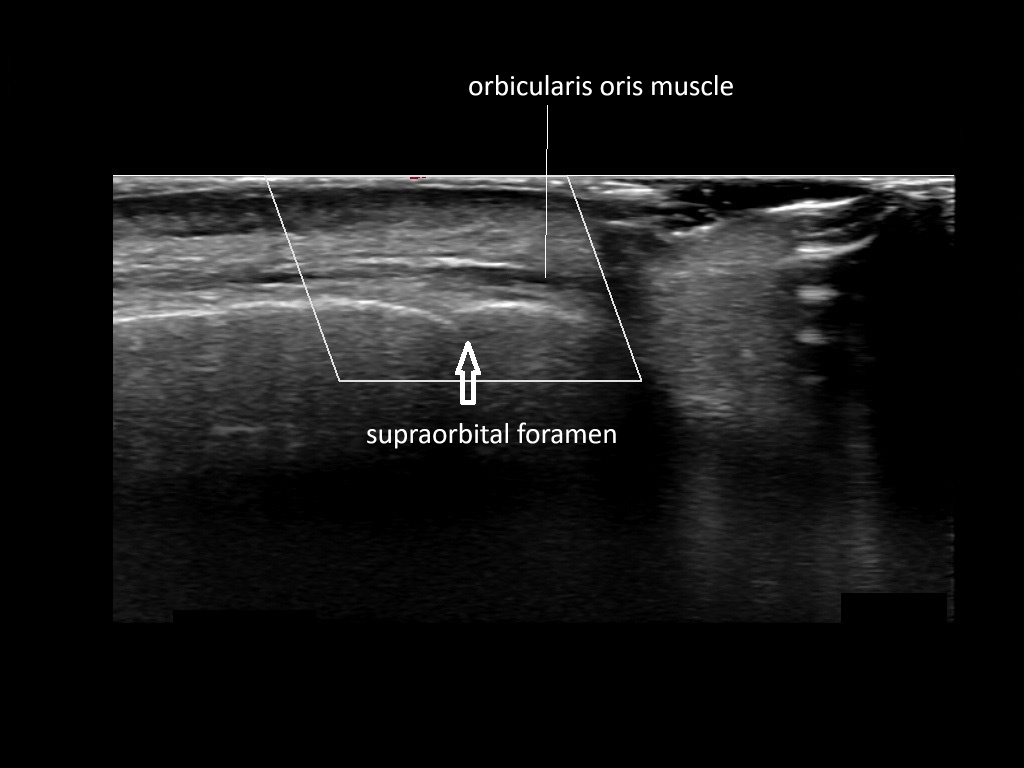

In this section you will learn more about the different layers of the face with the use of ultrasound. When you click on the secondary ultrasound image, you will see the different structures as an overlay. This will help to train yourself to recognize the different layers of the face.

Study the first image to recognize the different layers. If you are sure about the layers, swipe to the second image to view the answer (if applicable).